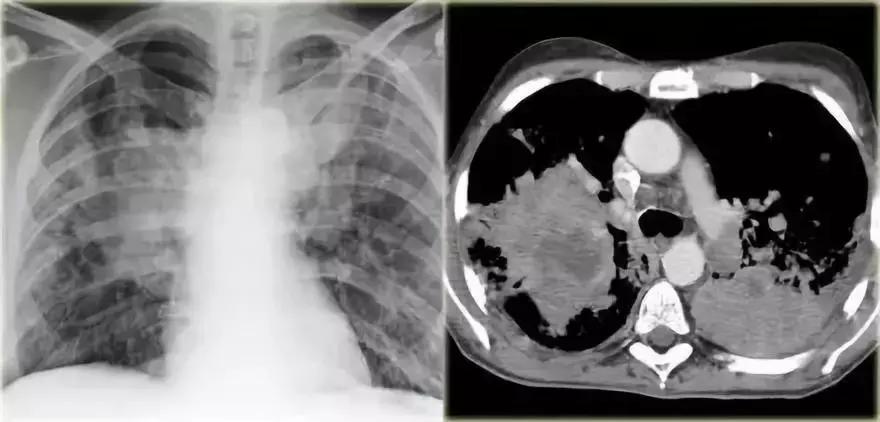

肺栓塞

➢ 急性非动脉血栓栓塞的影像图常变化不显著,而且非特异性。

➢ 对肺动脉血栓(PIOPED)的前瞻性研究发现最常见的影像学特征是肺不张和肺斑片状阴影。

➢ 大多数肺动脉栓塞可有正常的胸部X线

➢ 观察CECT,此患者患有肺栓塞

➢ 在栓塞区域发生外周实变,为栓塞区出血引起

图7 肺栓塞性实变